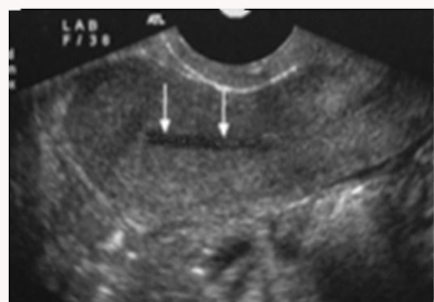

Identify the endometrial phase

During menstruation (may even see movement)